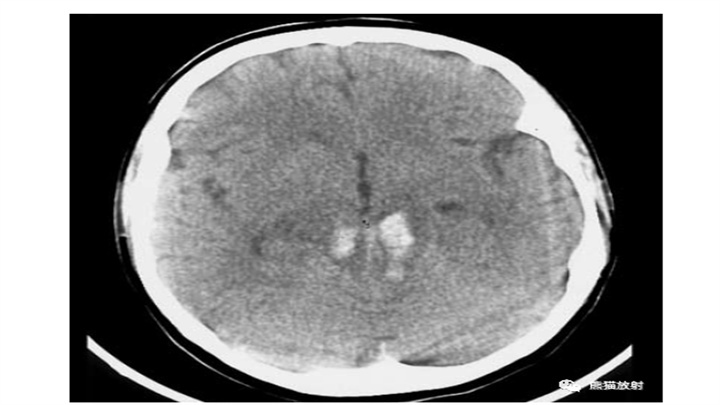

丘脑血肿,范围有限,保守治疗即可。对侧顶叶低密度楔形病变,陈旧性脑梗死。血肿占位效应明显(第三脑室变形)和脑室内积血,具有致命的后果。